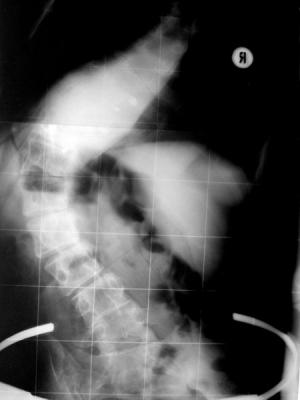

also das 1. Bild ist von Januar mit 92 und 40 und ca.20 grad.

Das 2. ist mein Höllenfahrtsergebniss :)

das 2. foto :)

mist, eigentlich müsste der Bogen in beiden Fällen nach links gehen..so das rechts das "loch" ist.

Man sieht wirklich eine sehr schöne Verbesserung. :zustimm:

Ich finde beim Röntgen im Korsett sieht man vor allem den Längen- oder besser gesagt Höhenunterschied der Wirbelsäule sehr schön.

Schaut echt gut aus, viel aufgerichteter eben :respect:.

Hallo Katrin, habe jetzt Röntgenbild Nr. 2 gespiegelt. ;) Man sieht vor allem im oberen Bereich die Verbsserung sehr schön. :)